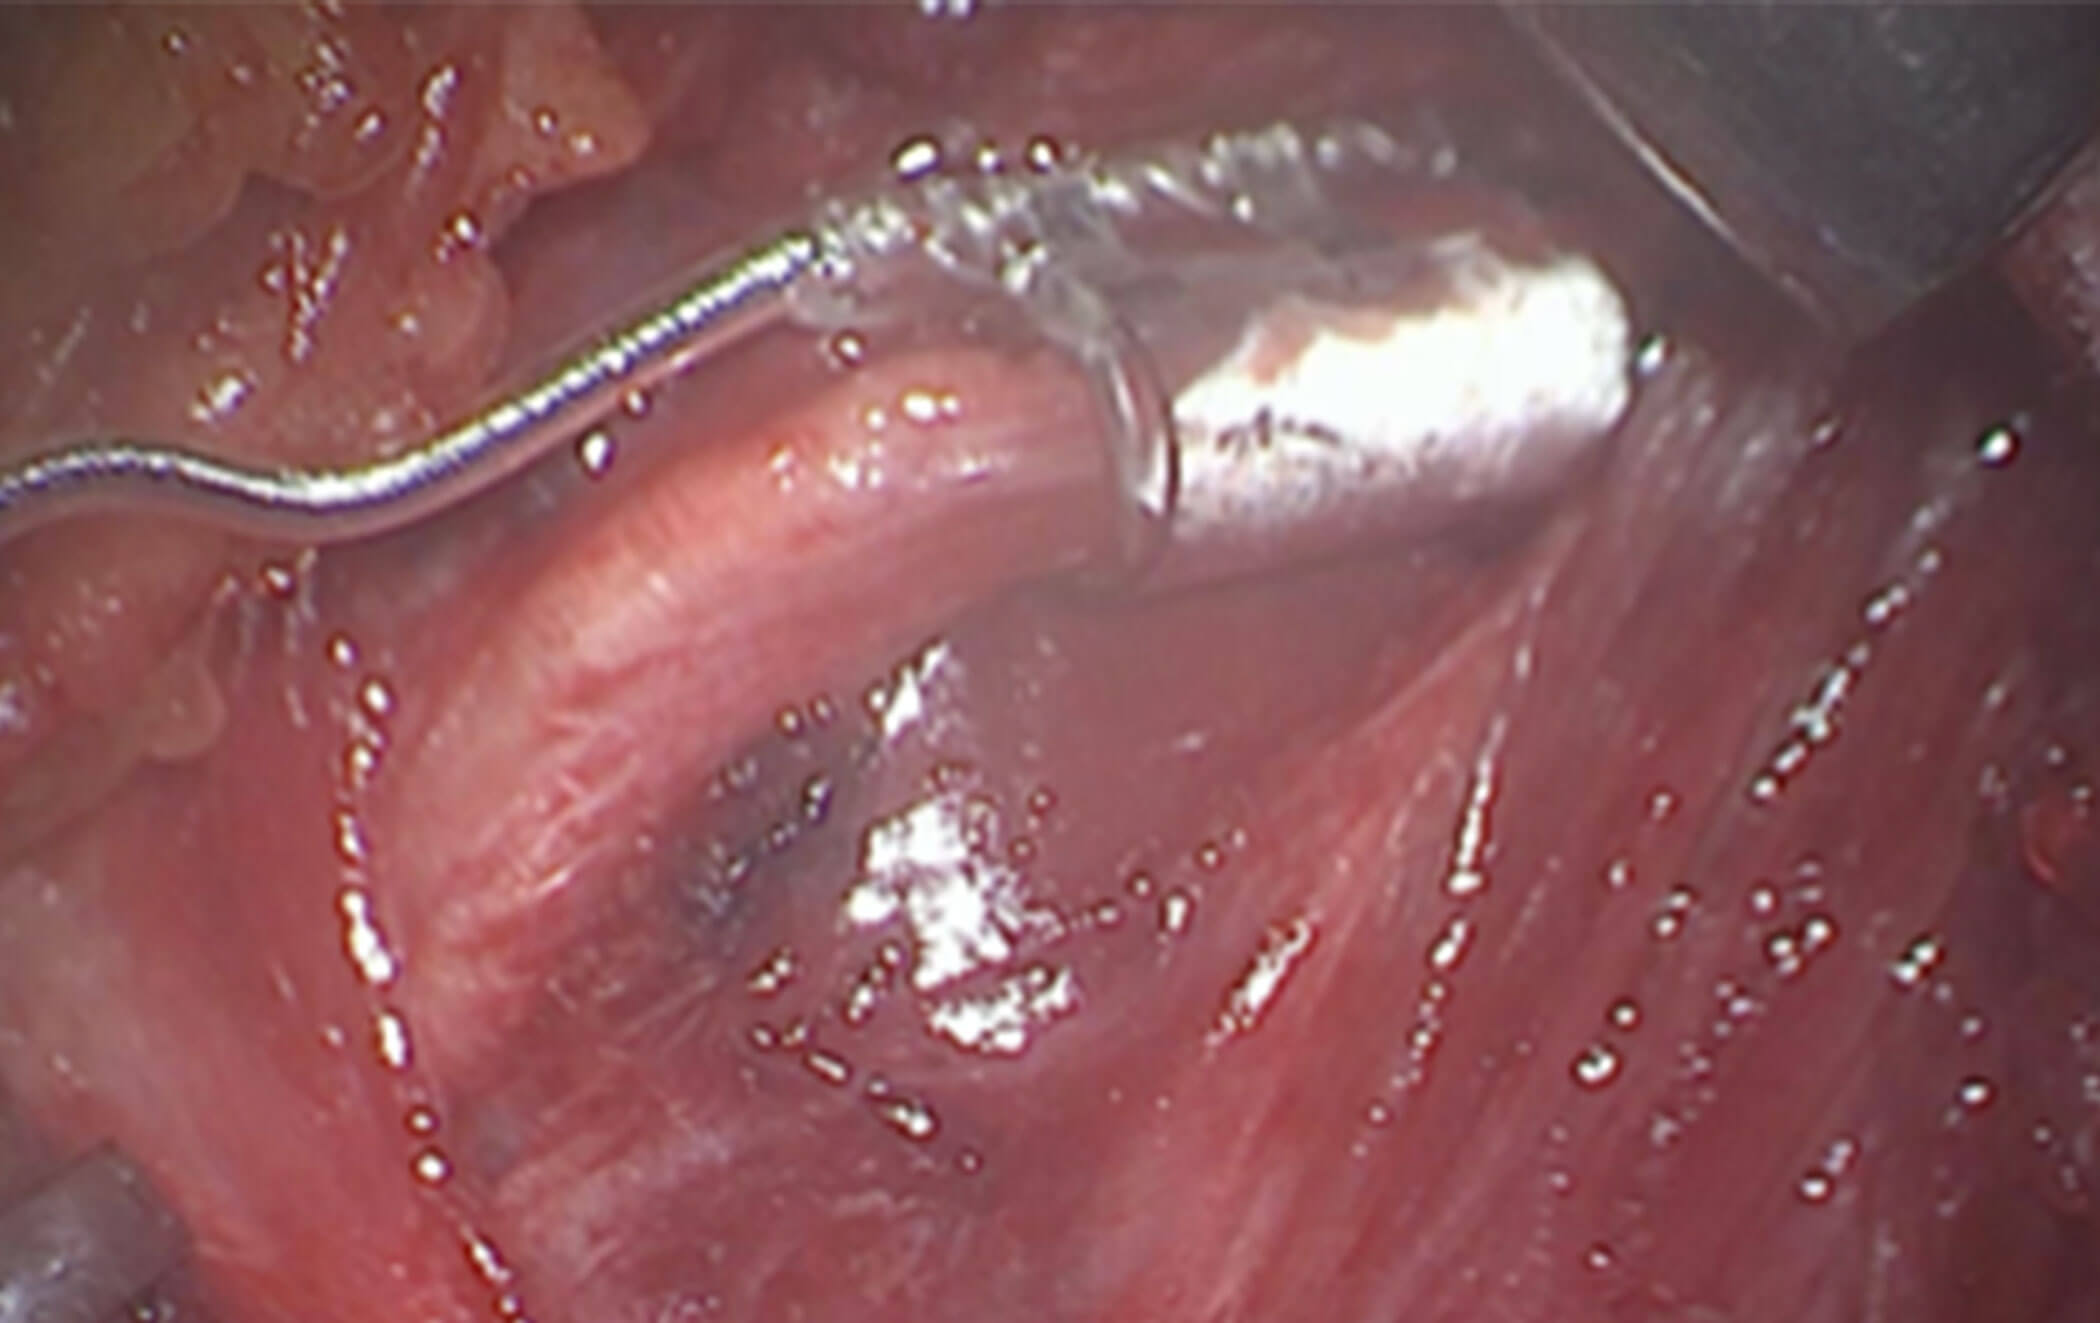

Figure 2b. Illustrating the nerve supply to tongue protrusion

muscle where the electrode cuff is placed.

Figure 2c. The electrode cuff is placed on the nerve supply to the genioglossus,

transverse and vertical muscle of the tongue and geniohyoid muscles.